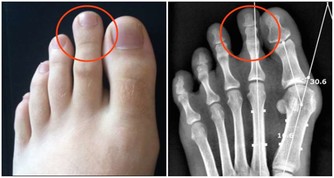

生老病死是人之常情,當人的年齡逐漸增大之後,身體的各個器官就開始漸漸衰老,生命也會漸漸失去活力。人在45歲之後。隨著我們的身體曰益衰老,心臟向全身輸送血液的效率也開始降低。這是因為血管逐漸失去彈性,動脈變硬或者出現阻塞。造成這些變化的原因是脂肪在冠狀動脈堆積,輸送到心臟的血液減少,有時會引起心絞痛。45歲以上的男性和55歲以上的女性心髒病發作的概率較大。